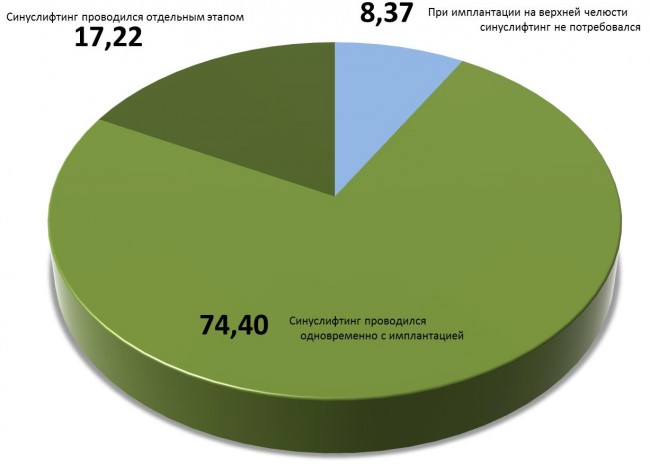

Я проанализировал собственную имплантологическую практику за 2012-2013 гг и изучил клинические случаи 418 пациентов, которым были проведены имплантологические вмешательства на верхней челюсти (имплантация, имплантация+синуслифтинг, синуслифтинг отдельным этапом). В результате, я получил следующие данные (рис 5):

То есть, при имплантации на верхней челюсти синуслифтинг (одномоментно или отдельным этапом) требуется почти в 92% случаев. Это делает его самой распространенной и востребованной остеопластической операцией в мире.